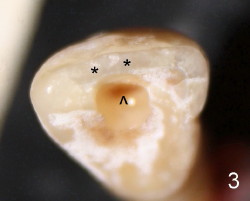

The tooth #8 of a 61-year-old man has obliterated canal probably due to trauma (Fig.1,2 (lateral view)). Initial access shows that the labial portion of the recessed pulpal horn (brown, < in Fig.3 (occlusal view) is not fully exposed, while that the most lingual aspect of the incisal edge (between **) has been removed. Further access appears to be necessary to expose the obliterated pulpal chamber (Fig.7 <) and more of the incisal edge has been violated ( between **). With good exposure, the canal is easily found around the arrowhead (<) in Fig.7. Laterally, the initial file: C6 is straight and slightly labial to the incisal edge (Fig.6). But it is somewhat bent in the front view (Fig.5). After enlargement of the coronal canal with Gates-Glidden files #2 and 3 (Fig.9<), #20 file appears to move distally (<-) and is straighter than the file in Fig.5. Laterally, the #20 file remains without much tension and around the incisal edge (Fig.10). Fig.11 shows occlusal view of the access after application of Gates-Glidden files. Before rotary files, the access is enlarged further both labially and lingually with diamond/carbide endo access burs (Fig.15). Fig.13,14 show 40/.04 file in the canal free without strain. The file seems to move distally further (Fig.13 <-).